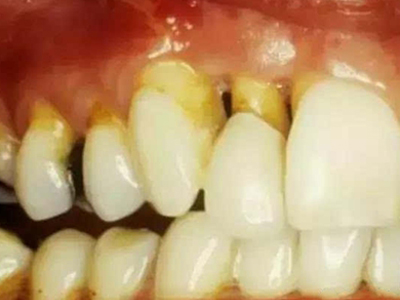

牙龈退缩牙根暴露出现黑斑图

牙龈退缩患者的上排多颗牙齿处的牙龈出现回缩,从而导致牙根外露,外露的牙根上存在黑色的牙菌斑、牙结石,伴有口臭、牙根面敏感等症状。